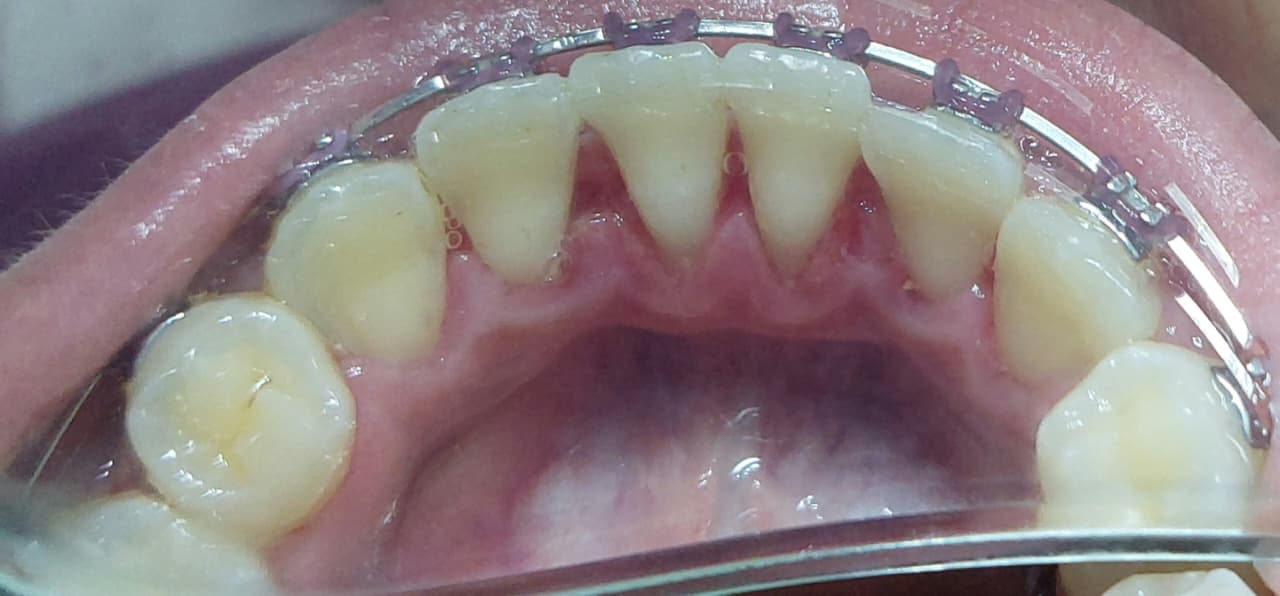

تنظيف الجير المتراكم

استعادة الابتسامة الكاملة و الحفاظ على صحة الاسنان